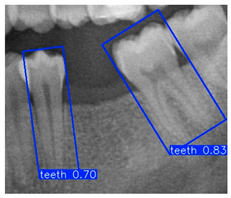

Further analysis revealed that although YOLOv11m performed slightly better on specific metrics, it was more prone to detection box shifts or overlaps in test images with complex backgrounds or blurred tooth boundaries, leading to reduced segmentation accuracy. As shown in Figure 10b, YOLOv11m produced detections with higher confidence scores; however, the predicted locations often deviated from the actual tooth positions. In contrast, Figure 10a illustrates that YOLOv9m, despite yielding slightly lower confidence scores, achieved superior localization accuracy with fewer false positives. This advantage was particularly evident in challenging cases involving blurred edges or narrow interdental spacing, where YOLOv9m consistently delivered stable predictions. The detection boxes generated by YOLOv9m provided higher accuracy and adhered more closely to the actual tooth contours, demonstrating greater stability and practical applicability. These strengths make YOLOv9m more suitable for subsequent fine-grained image segmentation and detailed dental structure analysis. Therefore, YOLOv9m was ultimately selected as the primary model for the following experiments, and all further applications and performance evaluations were conducted based on its outputs.

Figure 10.

Instance segmentation result comparison.